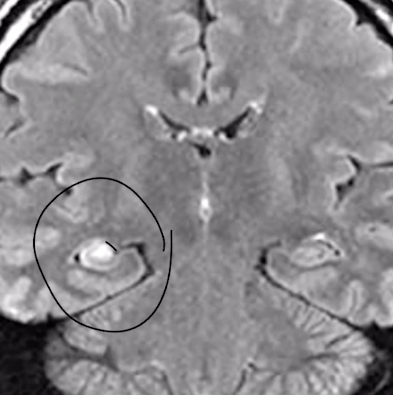

Esclerosis hipocampo

Hacia donde se desplazan lesiones en IX ( paladar )

Esclerosis mesial lóbulo temporal ( esclerosis hipocampo )